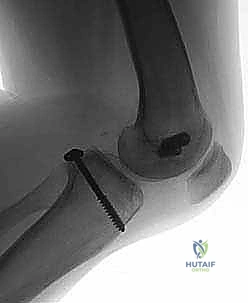

- الأشعة السينية (X-rays): لاستبعاد وجود كسور عظمية، خاصة كسور الانقلاع (Avulsion fractures) حيث ينفصل الرباط حاملاً معه قطعة من العظم.

5. الكسور الانقلاعية (Avulsion Fractures): حيث يحتاج العظم المنفصل إلى تثبيت فوري بالمسامير.